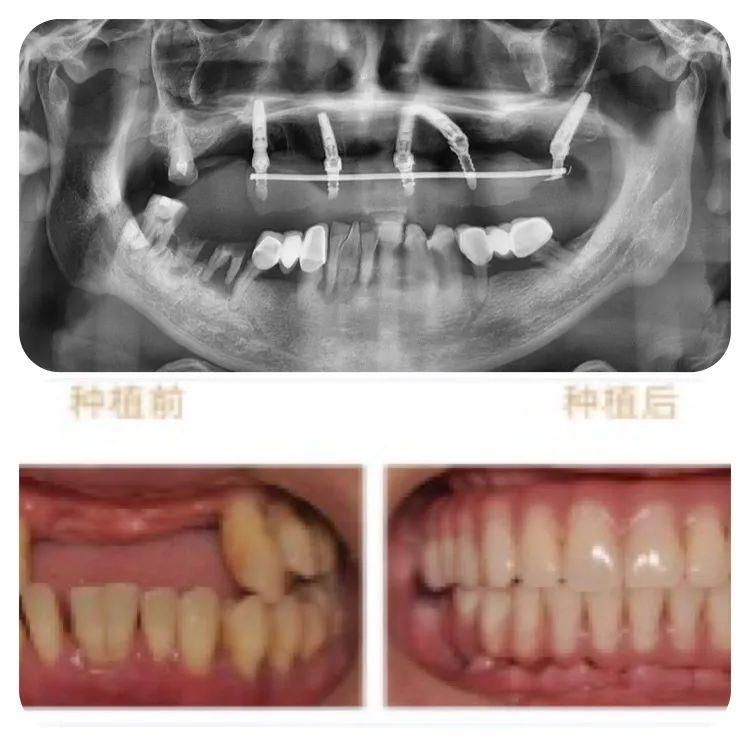

此次成功種牙的78歲高齡的老人,不但同時(shí)患有高血壓、心臟病及糖尿病,口腔條件也不容樂(lè)觀:因外傷引起牙缺失2年,有較嚴(yán)重的牙周炎,是典型的高齡疑難種牙案例。

診療方案

針對(duì)老人的口腔條件,重慶泰康拜博口腔VIP種植工作室通過(guò)3D數(shù)字化種植設(shè)計(jì)系統(tǒng)為他個(gè)性化計(jì)了帶1顆穿翼板種植的負(fù)重種植牙方案,即拔即種,全口牙在1天之內(nèi)完成了種牙、戴冠全過(guò)程,手術(shù)完成后帶上臨時(shí)牙冠,牙齒就已經(jīng)可以正常使用。

術(shù)后1周復(fù)查,通過(guò)口腔CT檢查,可以看見(jiàn)老人的種植牙、穩(wěn)固。老人自己也描述,他在種牙的時(shí)候感覺(jué)輕松快速,幾乎沒(méi)有痛感,打個(gè)盹的功夫,牙齒就種好了。